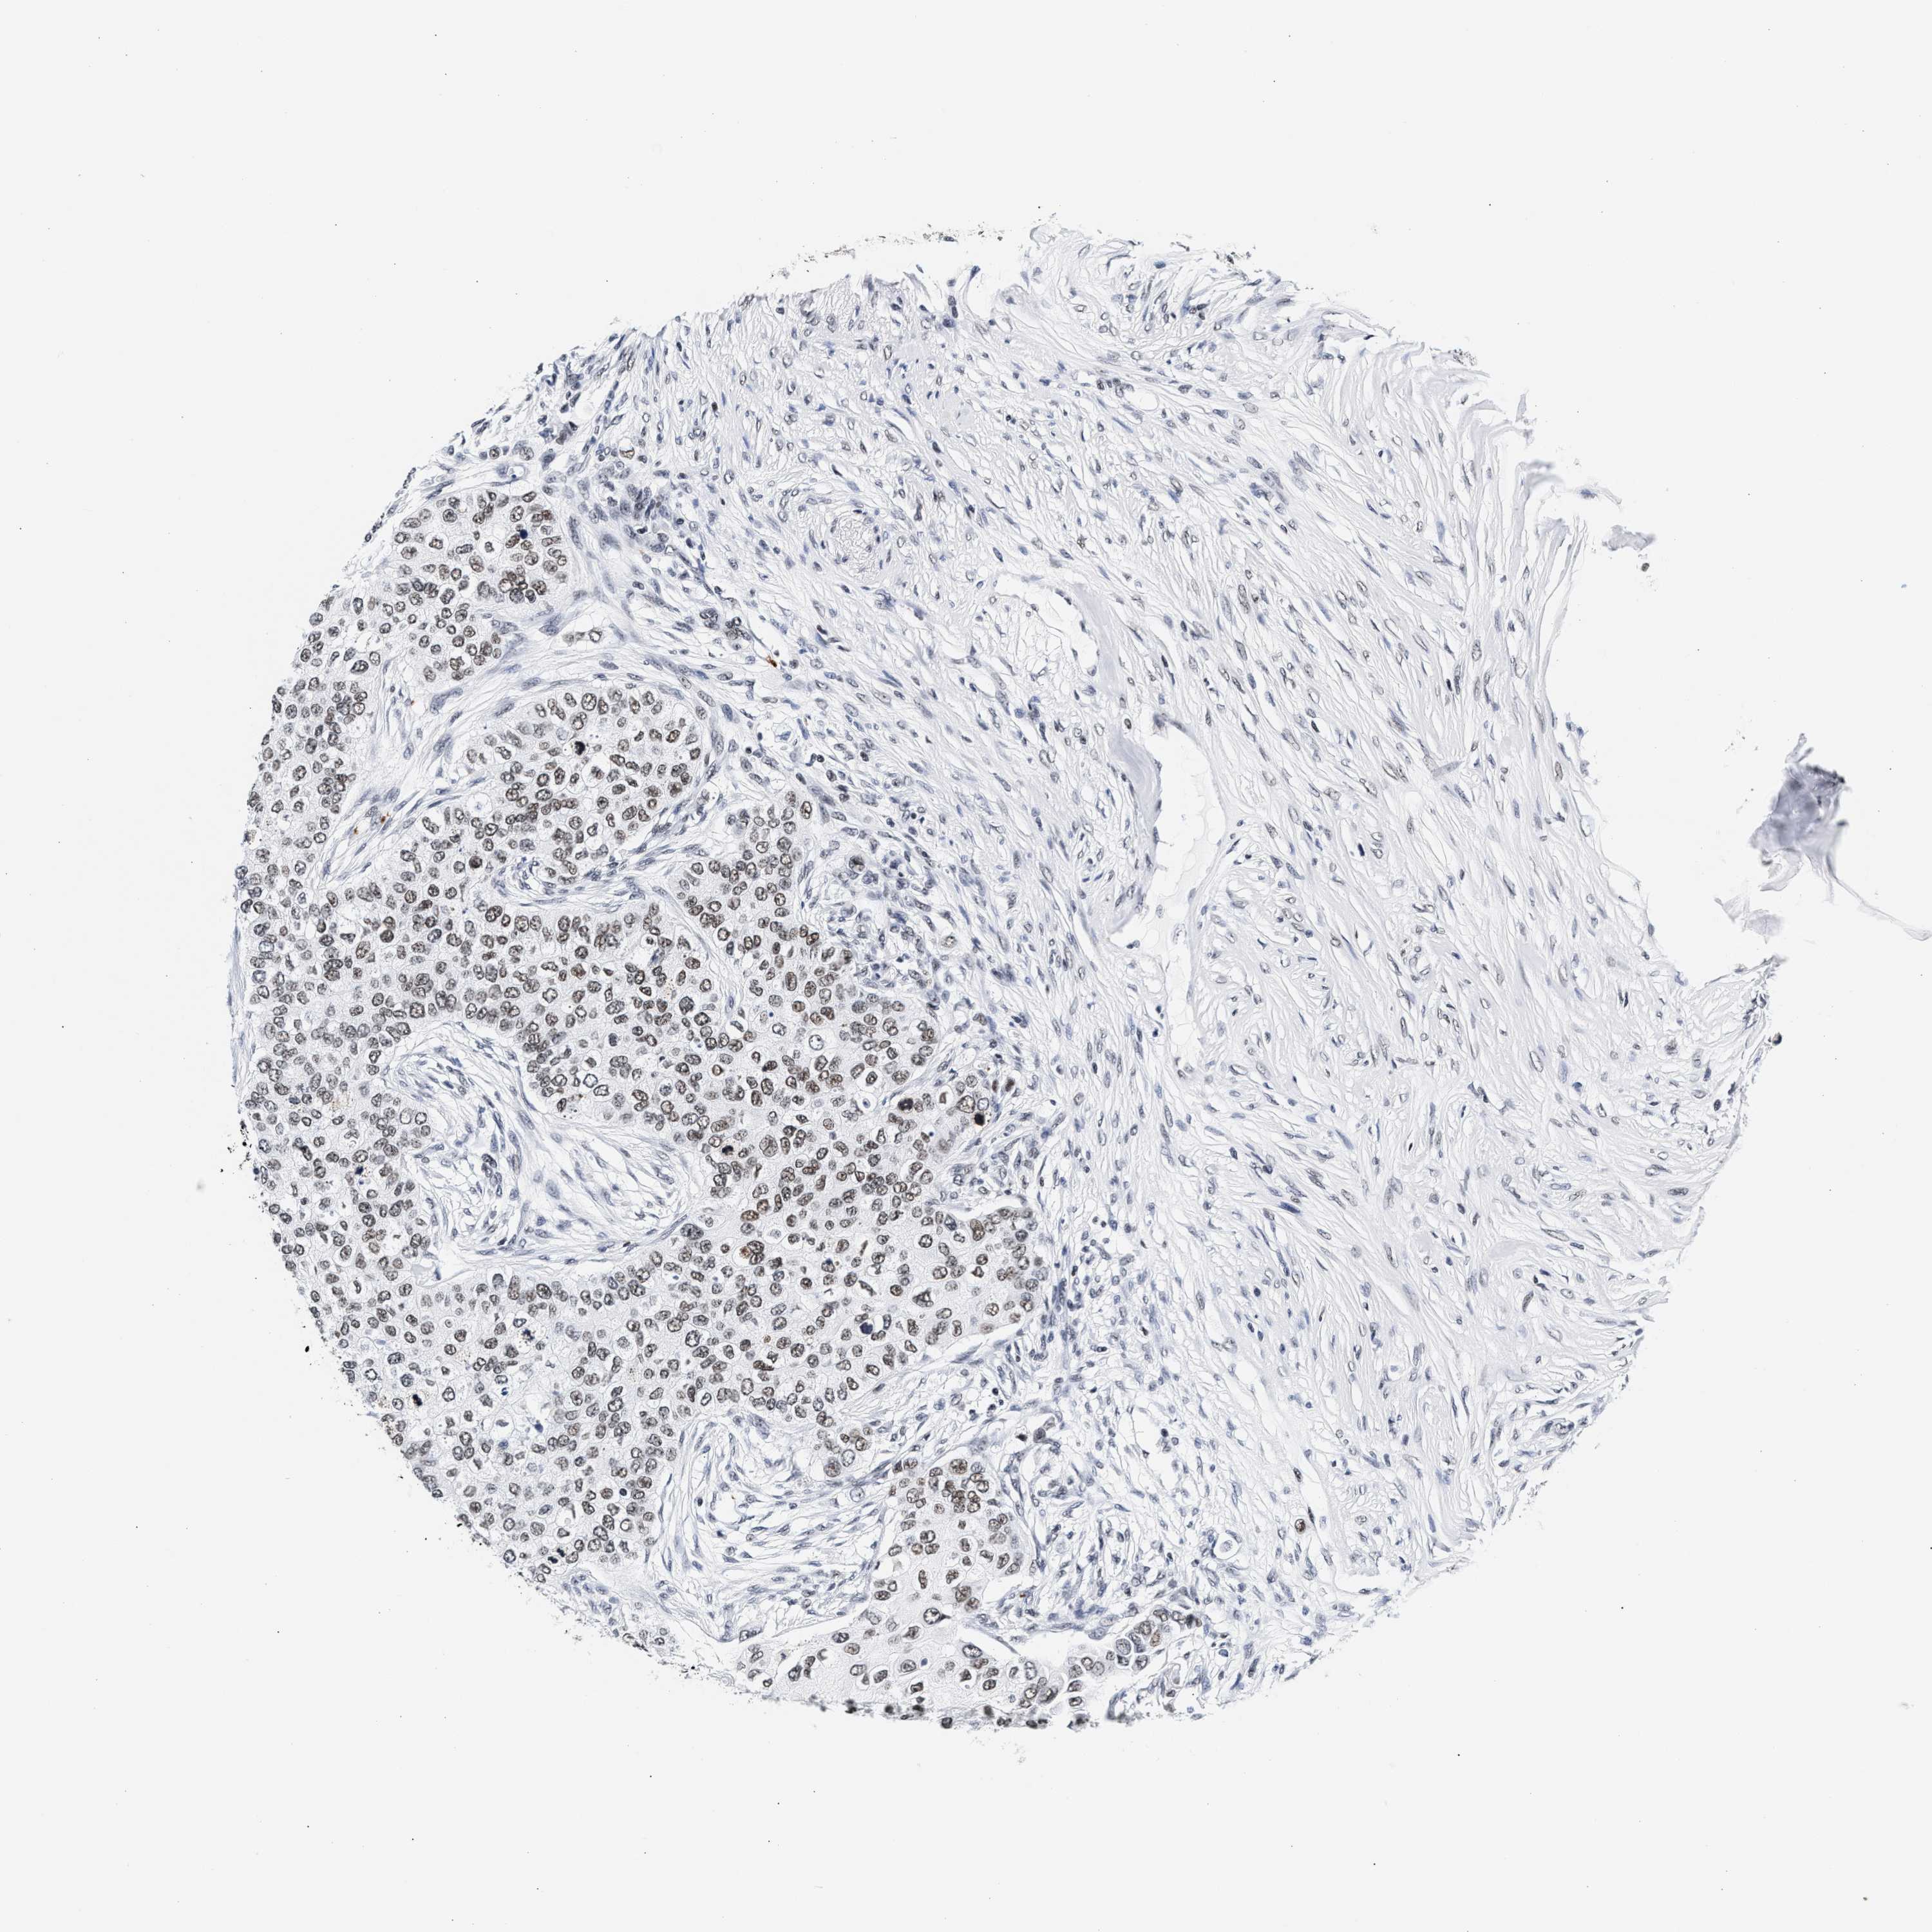

CANCER BREAST CANCER Show tissue menu

BRCA TCGA BRCA VALIDATION PROTEIN EXPRESSION